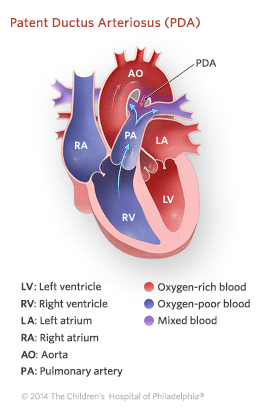

PDA Pathophysiology and Anatomy

Patent Ductus Arteriosus PDA Children s Hospital of Philadelphia

Patent Ductus Arteriosus PDA Rady Children s Hospital

PATENT DUCTUS ARTERIOSUS PDA IN CHILDREN Dr Gaurav Agrawal

What is PDA in Newborn Babies

Patent Ductus Arteriosus PDA Kauvery Hospital

Patent Ductus Arteriosus PDA in the newborn

Patent Ductus Arteriosus PDA Conditions amp Treatments Minnesota

Patent Ductus Arteriosus Pediatric Heart Specialists

Patent Ductus Arteriosus PDA for Parents Nemours Kidshealth

Patent Ductus Arteriosus PDA Symptoms and Risk Factors Dr Raghu

Pediatric Patent Ductus Arteriosus PDA

Patent Ductus Arteriosus Children s Hospital of Orange County